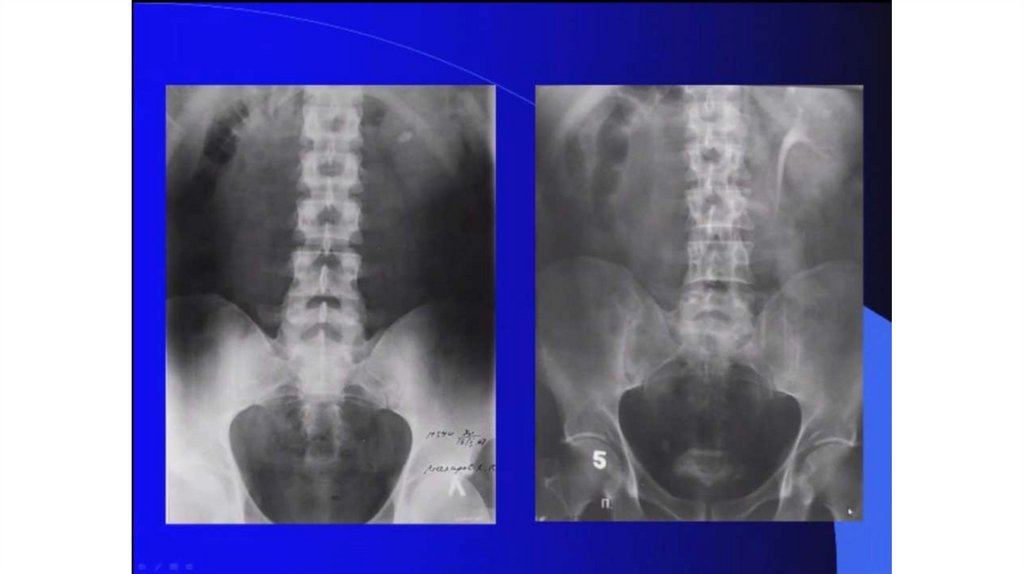

Мочекаменная болезнь. Мочекаменная болезнь и беременность

Мочекаменная болезнь